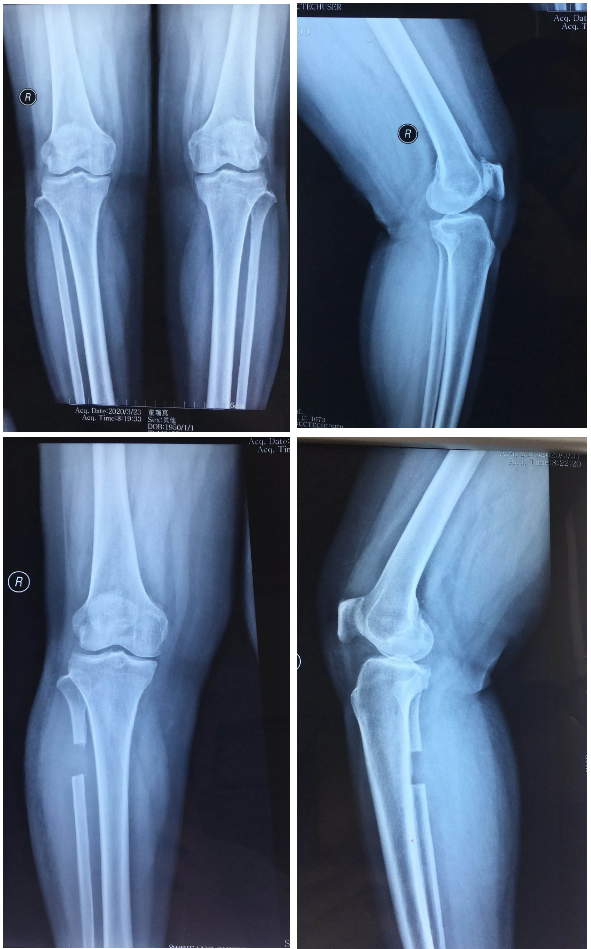

保膝治療

膝骨關(guān)節(jié)炎患者是臨床常見的老年關(guān)節(jié)疾病,骨二科根據(jù)患者病情綜合評估考量,對較年輕患者采用膝關(guān)節(jié)鏡清理加腓骨截骨術(shù),對脛骨近端內(nèi)翻畸形且外側(cè)關(guān)節(jié)間隙良好的患者采用膝關(guān)節(jié)鏡清理加脛骨近端高位截骨術(shù)或單髁置換術(shù),恢復(fù)患者膝關(guān)節(jié)正常力線,減緩或避免最終的膝關(guān)節(jié)置換治療。

腓骨截骨術(shù)

單踝置換